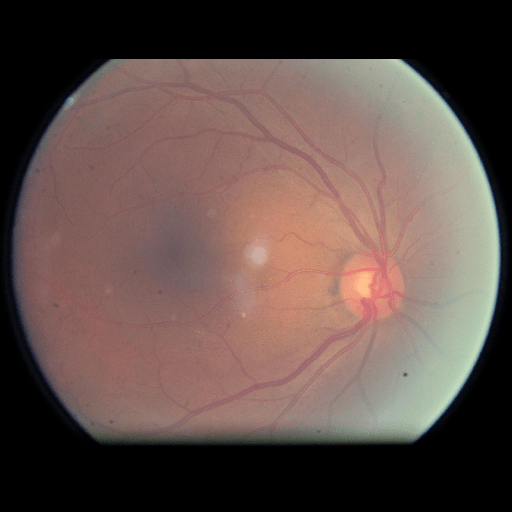

We conducted a case study on diagnosing diabetic retinopathy with ensembles of DL models. For benchmarking the performance of our ensemble-based solutions under the scheme described in Sec.3.3, we used two popular collections of diabetic retinopathy image data, the Kaggle Diabetic Retinopathy dataset [22] (hereafter referred to as “Kaggle-DR”) and the Messidor-2 dataset [23], each respectively consisting of and high resolution images. Diabetic retinopathy is graded into five SLs, as displayed in Figure 2. Following the problem setup used in previous papers [24], we trained models to distinguish the referable (SL2-4) cases from the non-referable ones (SL0 & SL1) (see Section B.1 for more detailed descriptions). We also tested our trained ensemble models on two o.o.d. image datasets (ImageNet [25] and CIFAR-10 [26]) to examine their capabilities of identifying o.o.d. inputs (see Section B in the supplementary materials).

The Kaggle-DR dataset comprises high resolution images. The presence of diabetic retinopathy is rated into five different SLs: no-DR (SL0), mild (SL1), moderate (SL2), severe (SL3), and proliferate (SL4), as illustrated in Figure 2. We divided the Kaggle-DR dataset into a development set and a test set, which respectively consisted of and images. The data in the development set were used to train and validate our Deep Learning (DL) models. The Messidor-2 dataset [38] that consisted of images was also used in our experiment as an additional dataset to test the true generalization performance of the models trained on the Kaggle-DR dataset. Images in Messidor-2 dataset were graded into the five SLs as in the Kaggle-DR dataset. Figure S.1 provides an illustration of the datasets used in our experiments.